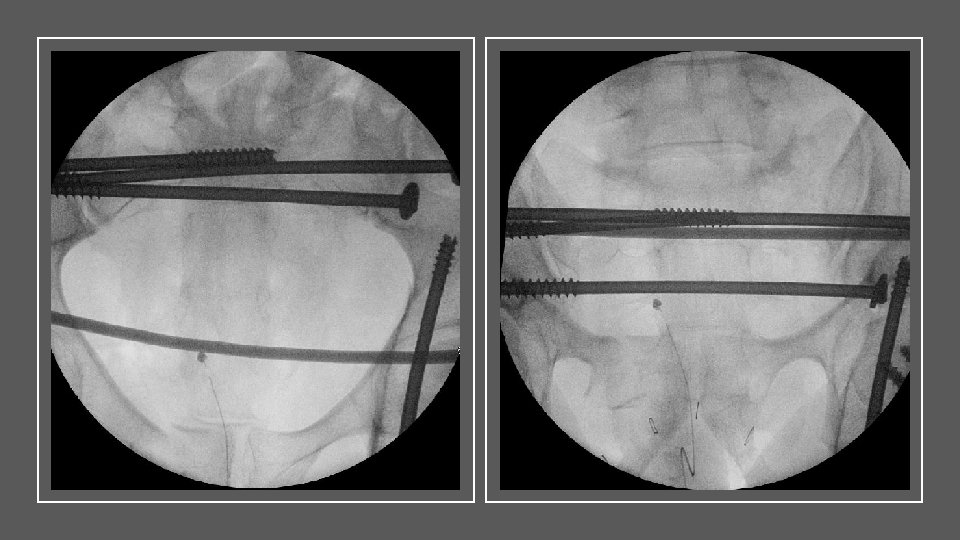

CASE 2: EARLY APPROPRIATE CARE SKELETAL PHYSIOLOGICAL ASSISTANCE • SKELETAL PHYSIOLOGICAL ASSISTANCE

Minimally invasive techniques KEY MESSAG E CASE 2 Beware the multiple long bone patient

Minimally invasive techniques KEY MESSAG E CASE 2 Beware the multiple long bone patient Regular reassessment through the case Keep the surgical hit to a minimum